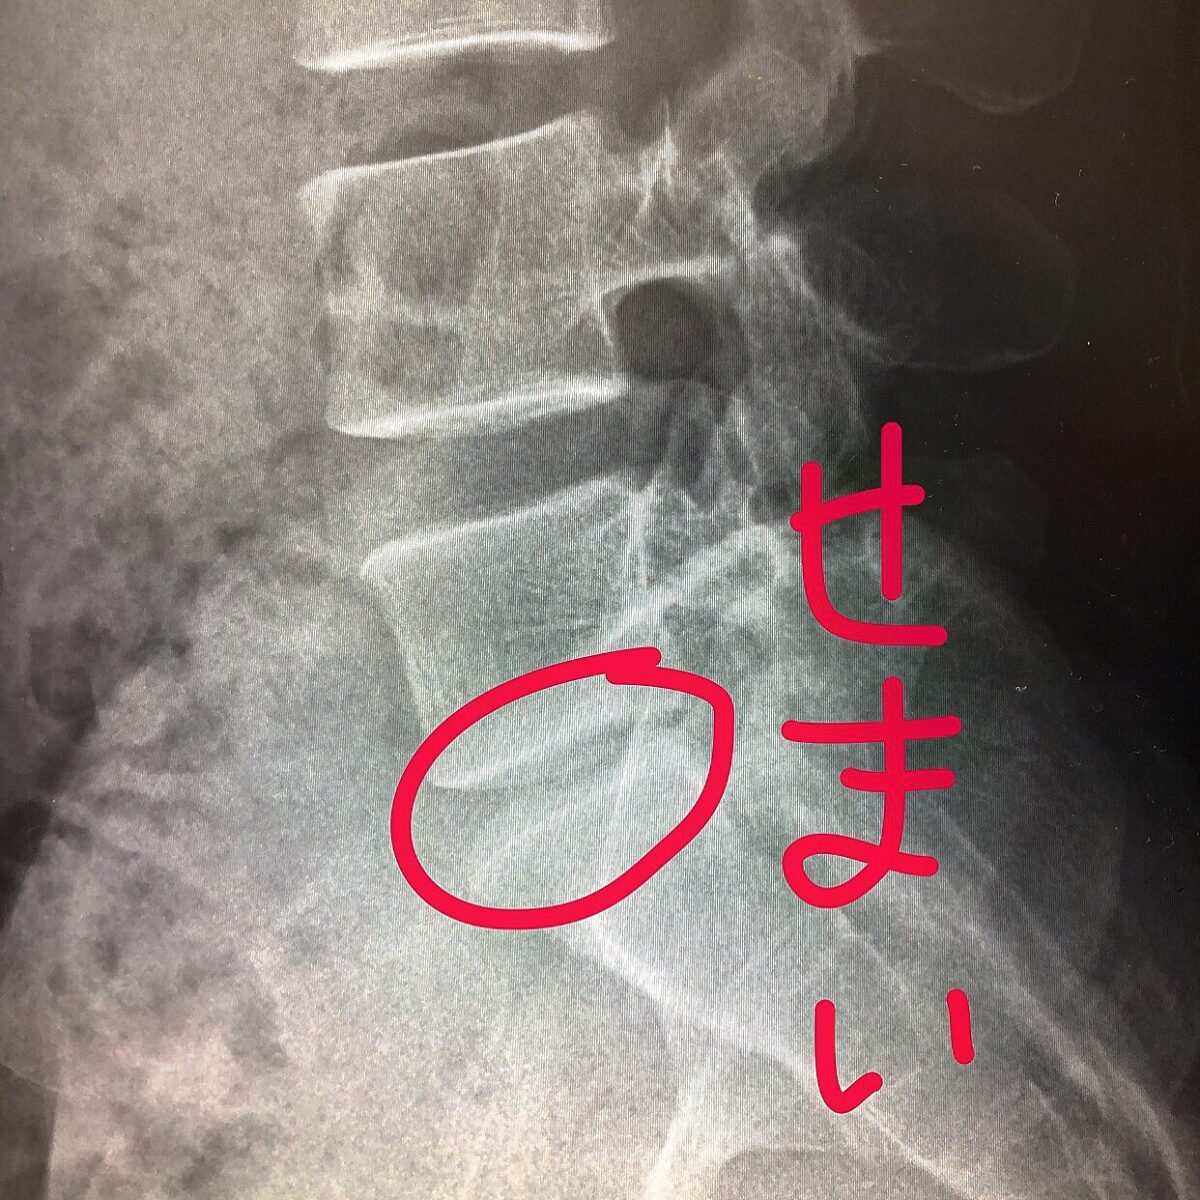

レントゲンと理学療法士によるリハビリ。

腰椎の1つの間隔が狭い(ヘルニア)ので腰に負担がかかりやすく腰痛がおきて、更に腰の痛みが脚にきているのだろう、とのこと。

まずは整形外科でふたたびレントゲン

ヘルニアですねー